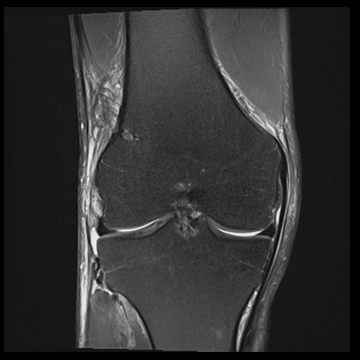

膝関節

PD 脂肪抑制

T1 TSE

3D TrueFISP脂肪抑制

MRI画像例

左右にスクロールして画像をご覧いただけます。